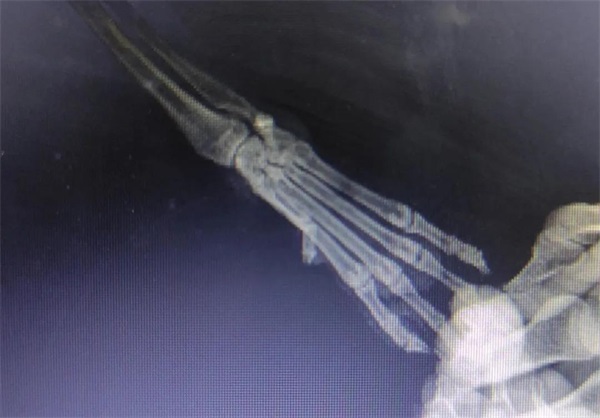

¡¡¡¡¾È»¤Ö°Ô±ÅжÏËüÊÇÐÛÐÔ£¬ £¬£¬£¬£¬£¬ÑdzÉÌå¡£¡£¡£¡£¡ £»£»£»£»£»£»£»Øµ½¾È»¤ÖÐÐĺó£¬ £¬£¬£¬£¬£¬¾È»¤Ö°Ô±Á¬Ã¦¶ÔËüµÄÊÜÉ˲¿Î»¾ÙÐÐÁËX¹âÅÄÉã¼ì²é£¬ £¬£¬£¬£¬£¬É¨³ý¹ÇÕÛ¿ÉÄÜ£¬ £¬£¬£¬£¬£¬Ëæºó¶ÔÍâÉË´¦¾ÙÐÐÇå´´Ïû¶¾£¬ £¬£¬£¬£¬£¬·ìºÏÆÆËðÆ¤·ô¼°½Åµæ¡£¡£¡£¡£¡£Ö®ºó¾ÙÐÐÁËͨÀýÌå¼ì£¬ £¬£¬£¬£¬£¬È·Èϲ¢ÎÞÆäËûÎÊÌ⣬ £¬£¬£¬£¬£¬ÏȺóÔھȻ¤ÖÐÐĵÄÖÎÁÆÇø¡¢¿µ¸´ÇøÉúÑÄ¡£¡£¡£¡£¡£

·Å¹éǰÌå¼ì£º×óÊÖ»Ö¸´µÄºÜºÃ